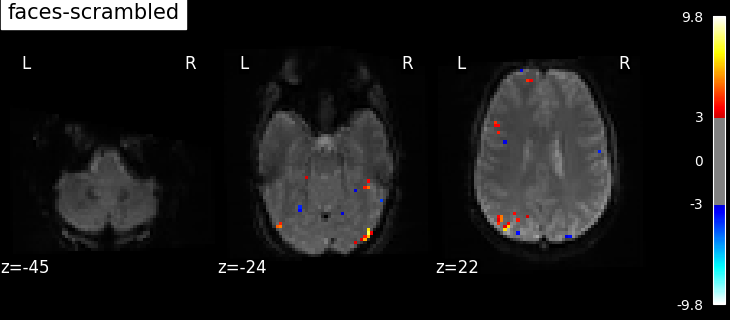

Now we can compute contrast-related statistical maps (in z-scale), and plot them.

for contrast_id, contrast_val in contrasts.items():

z_map = fmri_glm.compute_contrast(contrast_val, output_type="z_score")

plotting.plot_stat_map(

z_map,

bg_img=mean_image,

threshold=3.0,

display_mode="z",

cut_coords=3,

black_bg=True,

title=contrast_id,

)

contrast id: faces-scrambled

Based on the resulting maps we observe that the analysis results in wide activity for the ‘effects of interest’ contrast, showing the implications of large portions of the visual cortex in the conditions. By contrast, the differential effect between “faces” and “scrambled” involves sparser, more anterior and lateral regions. It also displays some responses in the frontal lobe.